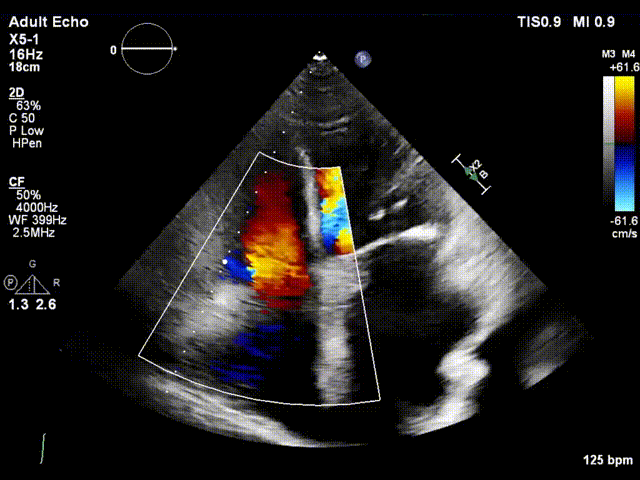

术前超声

术后超声